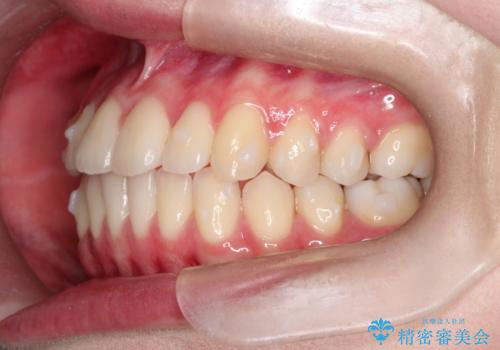

インビザラインによる非抜歯矯正 ガタガタな歯並びを整った歯並びへ

- 前歯のガタガタを主訴に来院されました。

抜歯矯正も考えられる状態でしたが、非抜歯矯正を希望されました。

使用時間を守っていただけたので、スムーズに治療を終わることができました。